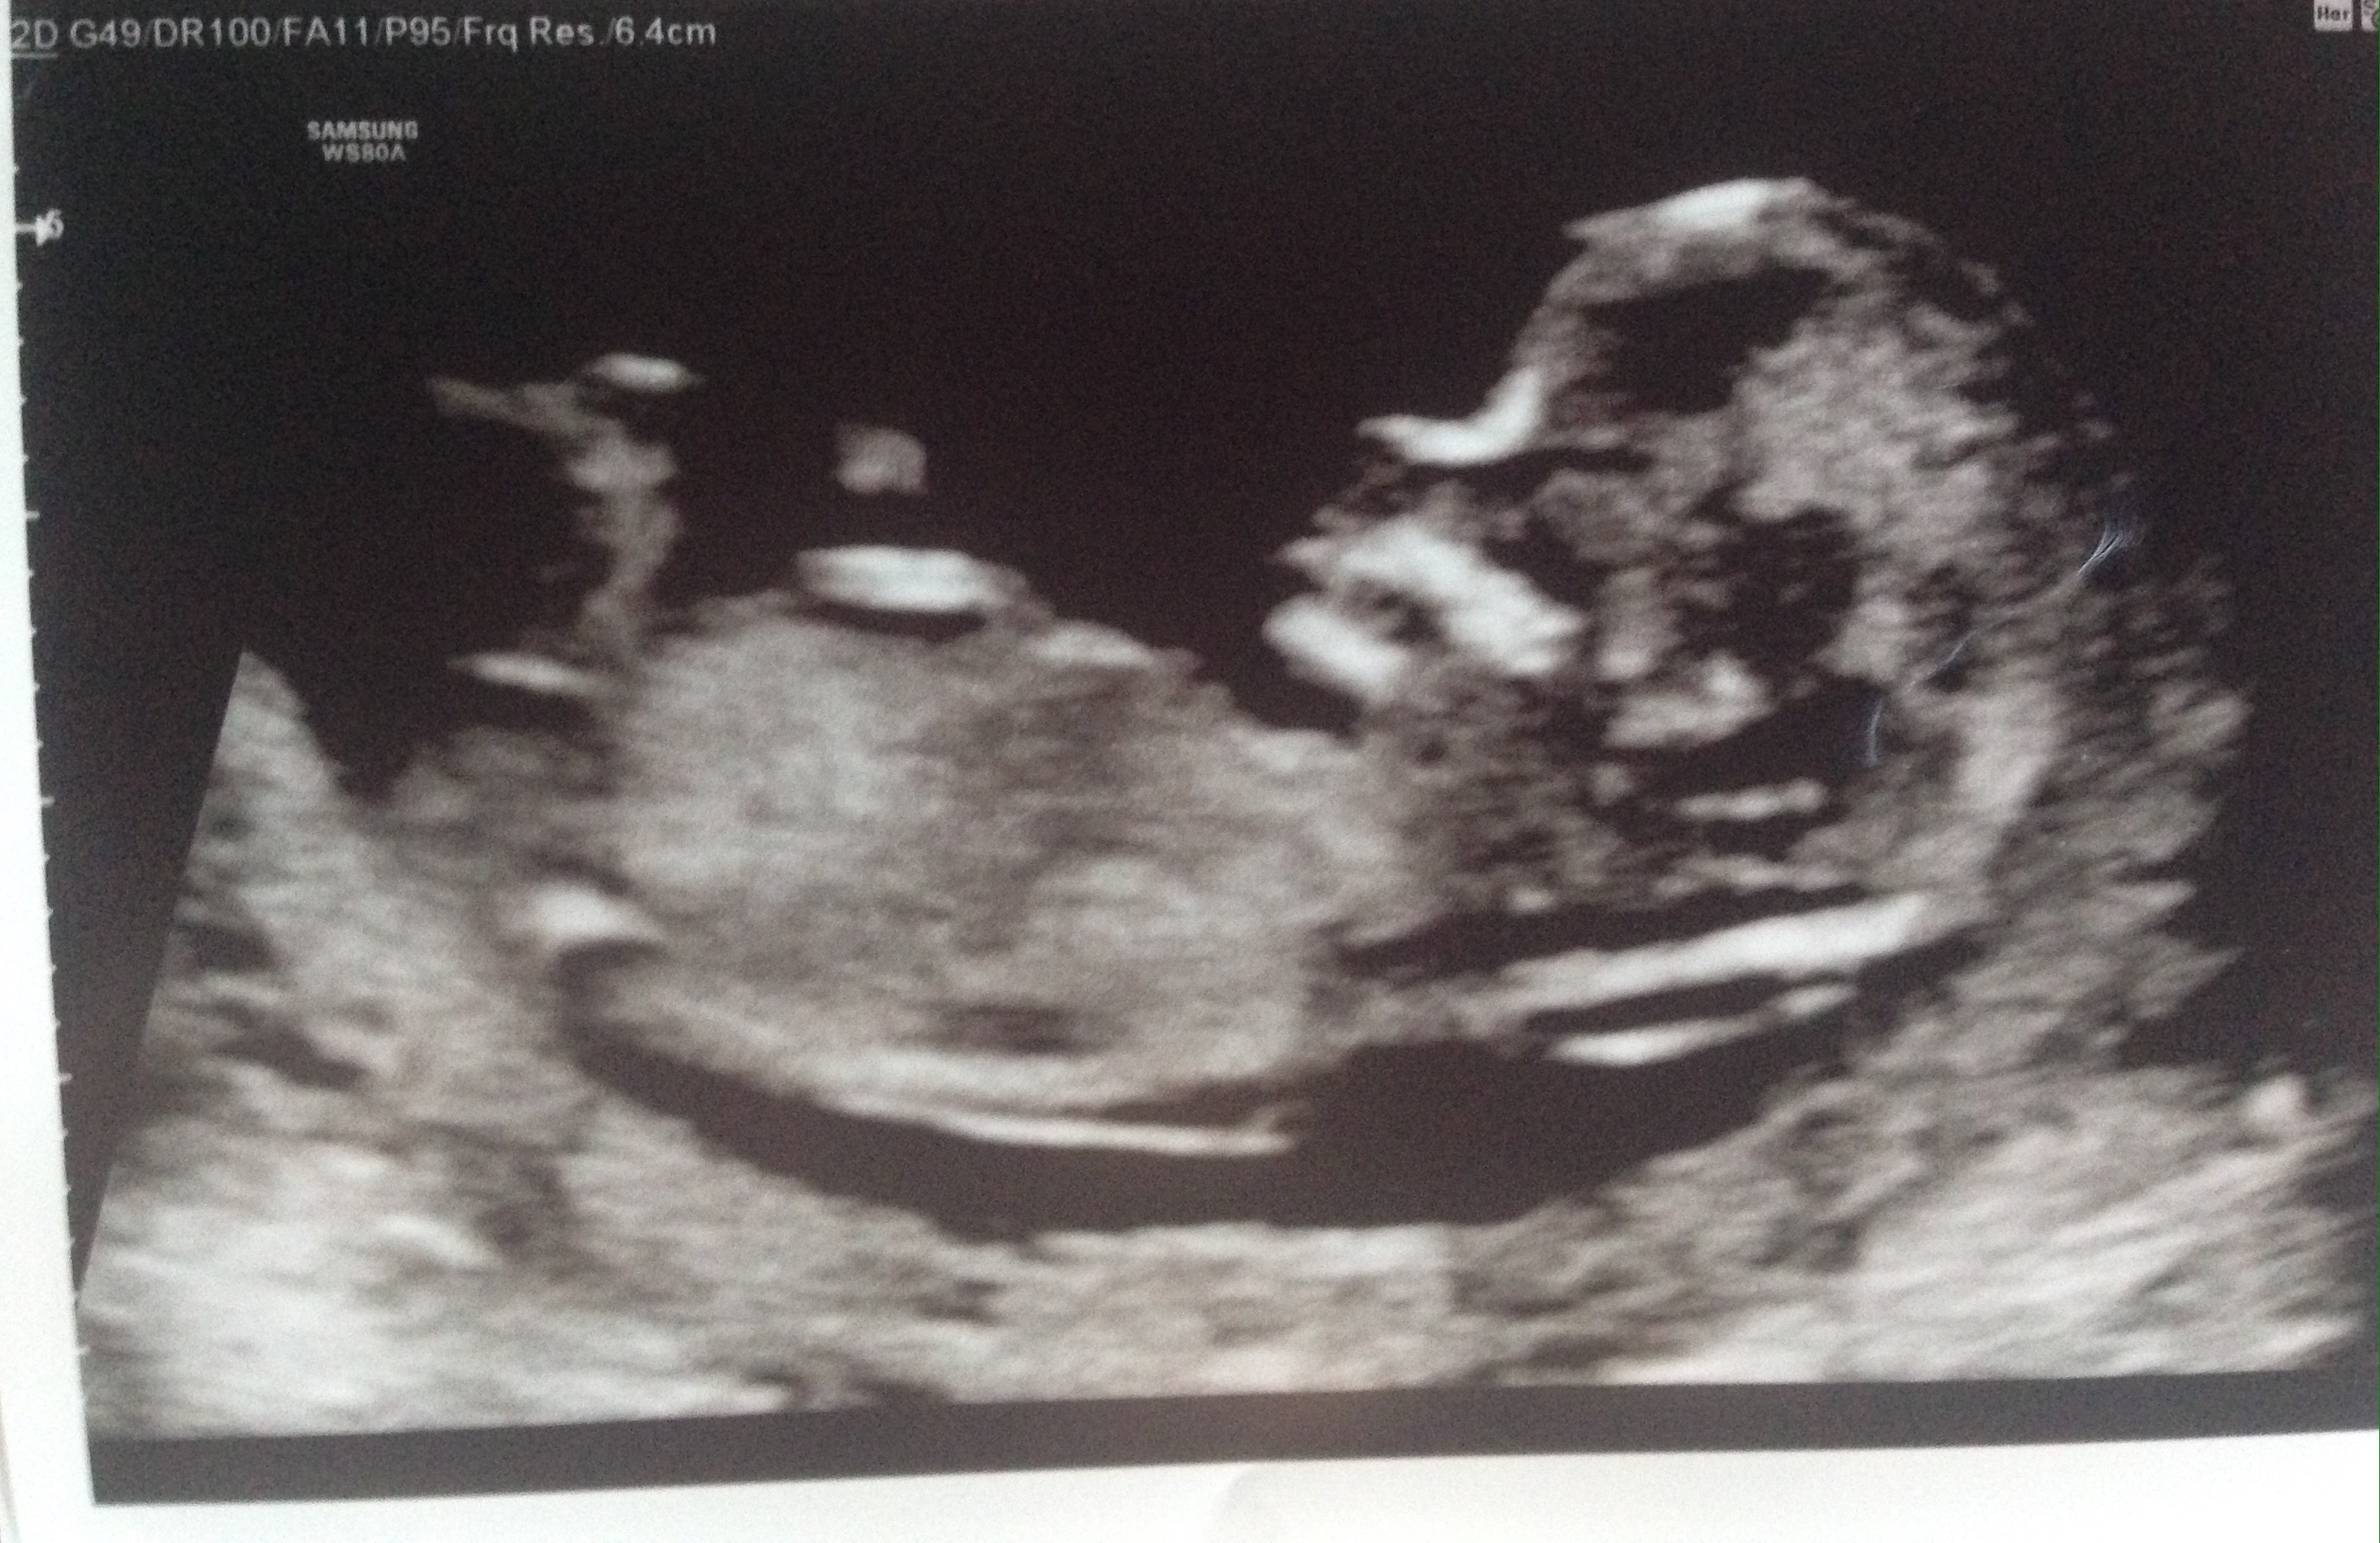

Since I couldn’t post any baby related pictures over the last 13 weeks I’ve posted some below to help catch you up. Over the next few months I’ll try to keep you guys updated on the highs and lows of pregnancy so stay tuned!